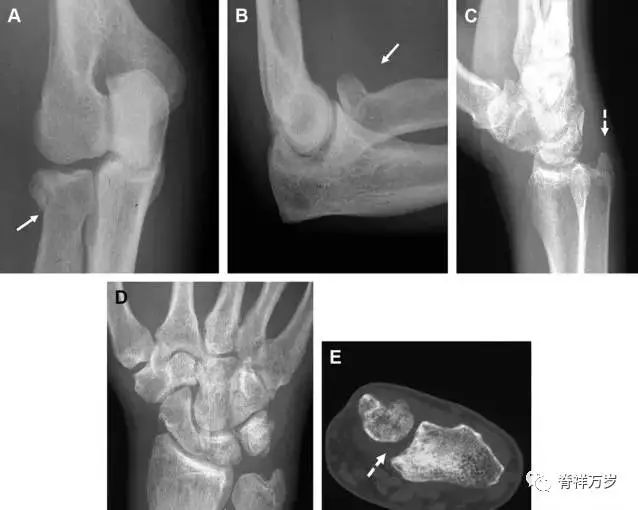

多发生于摔倒时,手掌撑地,受到轴向、外翻应力所致。常规的前后位片容易漏诊,常需加拍内斜位、外斜位、桡骨头-肱骨小头位片。后脂肪垫可见(位于鹰嘴窝内,一般不可见)和/或前脂肪垫抬高常提示骨性损伤。

图 2 桡骨头骨折。前后位(A)和侧位(B)片示后脂肪垫抬高(黑色箭头),前脂肪垫抬高(白色箭头),呈「帆船征」,其它表现正常;外斜位(C)和桡骨头–肱骨小头位(D)示桡骨头关节内骨折线(虚线黑箭头)累及桡骨颈(虚线白箭头)。

Essex-Lopresti 损伤

Essex-Lopresti 损伤是桡骨头骨折伴有下尺桡关节脱位,导致骨间膜损伤,桡骨短缩。此种损伤,桡骨头骨折的诊断往往是明确的,容易忽视的是下尺桡关节脱位,特别是早期,下尺桡关节的症状不明显,X 线表示也不明显。

图 8 Essex-Lopresti 损伤。前后位(A)和侧位(B)示桡骨头关节内骨折(白色实线箭头);(C~E)伤后 1 个月复诊,患者诉腕关节疼痛,X 线(C,D)发现下尺桡关节脱位,(E)CT 进一步证实损伤的存在。